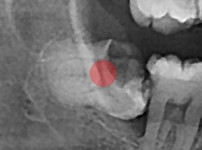

완전 매복 사랑니